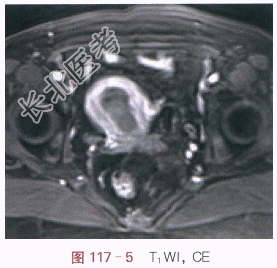

(1)症状:女,59岁,不规则阴道流血2月余。

(2)体格检查:诊断性刮宫未见异常。

影像学资料如图117-1~图117-5所示。

读片分析:子宫稍增大,内膜弥漫性增厚,结合带中断。增强扫描后,增厚的内膜呈不规则强化,局部浸润超过肌层1/2厚度。